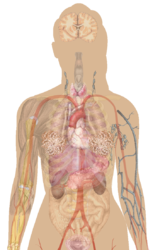

Human body diagramsMain article at: Human body diagrams Template location: Template:Human body diagrams How to derive an imageDerive directly from raster image with organsThe raster (.png format) images below have most commonly used organs already included, and text and lines can be added in almost any graphics editor. This is the easiest method, but does not leave any room for customizing what organs are shown.

Adding text and lines: Derive "from scratch"By this method, body diagrams can be derived by pasting organs into one of the "plain" body images shown below. This method requires a graphics editor that can handle transparent images, in order to avoid white squares around the organs when pasting onto the body image. Pictures of organs are found on the project's main page. These were originally adapted to fit the male shadow/silhouette.

Organs:

Derive by vector templateThe Vector templates below can be used to derive images with, for example, Inkscape. This is the method with the greatest potential. See Human body diagrams/Inkscape tutorial for a basic description in how to do this.